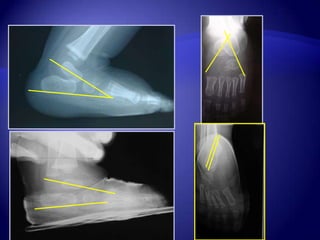

RAPPEL OSSIFICATION DU

PIED

- 3ème mois in utero:

métatarsiens et phalanges

- 24ème semaine : calcanéum

- 26ème semaine : talus

- à la naissance : cuboïde

- vers 4-5 ans : naviculaire

- 9 ans : ossification de la

tubérosité postérieure du

calcanéum

Inutile < 4 mois

Angle Tibio-calcanéen (ATC)

4 mois

ATC  75

ATC < 75

85

50